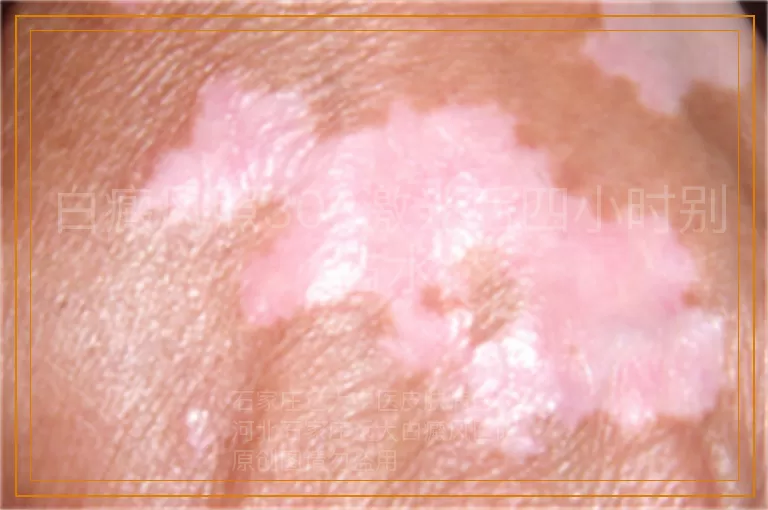

根据患者病情定制治疗方案,采取激光治疗+药物治疗,同时食疗辅助,一段时间后白斑开始变化,边缘出现明显黑色素岛。

一个月左右白斑边缘出现黑色素岛,根据恢复情况调整治疗方案,联合药物渗透治疗,提高药物吸收能力,缩短白斑恢复时间,直至白斑完全复色